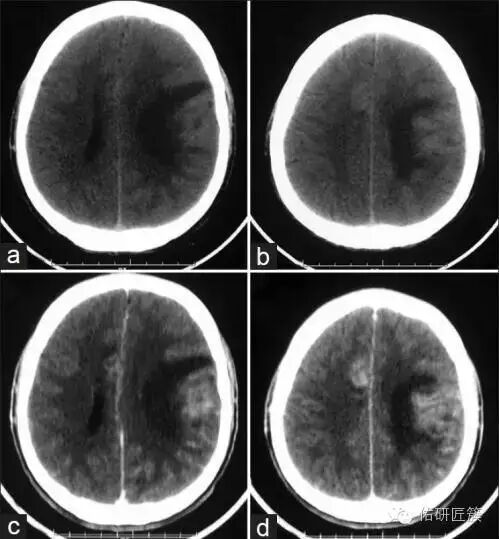

這些因素引發(fā)混合感染,導(dǎo)致腦膿腫、出血,并最終導(dǎo)致腦組織壞死!

醫(yī)學(xué)家對(duì)阿米巴性腦膜腦炎患者的尸檢發(fā)現(xiàn),病變部位多集中于大腦,腦積液中能發(fā)現(xiàn)蟲(chóng)體;患者的鼻腔粘膜和穿過(guò)篩板的嗅神經(jīng)也有嚴(yán)重的炎性損害,并可發(fā)現(xiàn)蟲(chóng)體。而身體的其他部位未發(fā)現(xiàn)蟲(chóng)體。

患者腦積液中可見(jiàn)“食腦蟲(chóng)” 圖/網(wǎng)絡(luò)